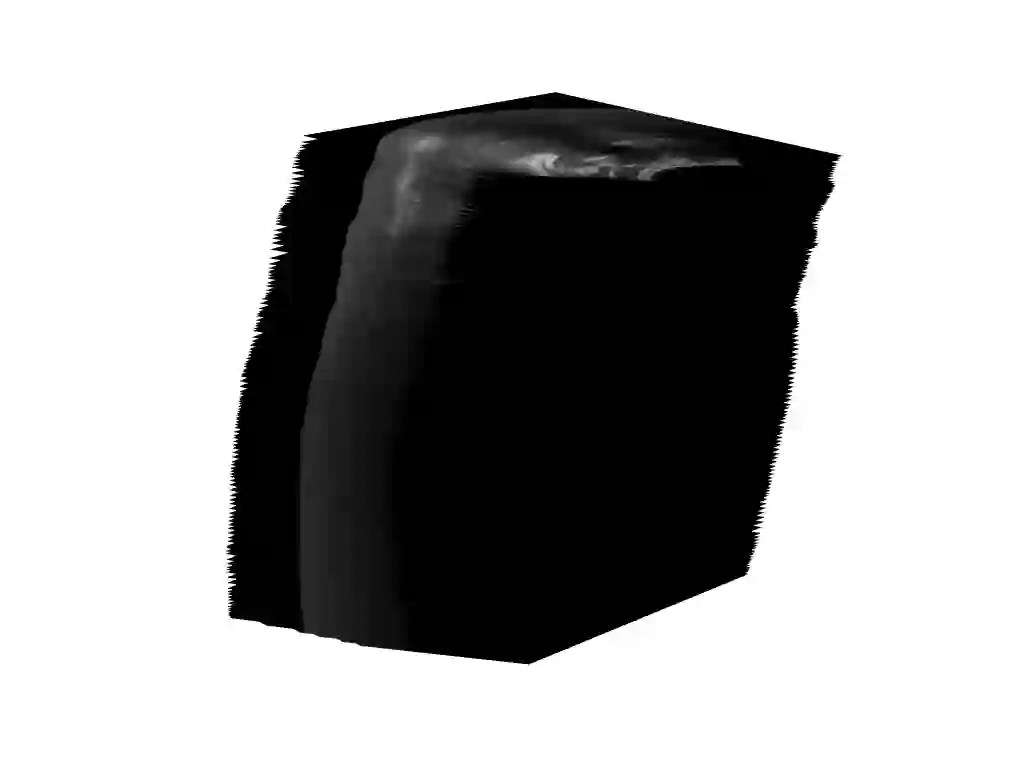

Three-dimensional (3D) freehand ultrasound (US) reconstruction without a tracker can be advantageous over its two-dimensional or tracked counterparts in many clinical applications. In this paper, we propose to estimate 3D spatial transformation between US frames from both past and future 2D images, using feed-forward and recurrent neural networks (RNNs). With the temporally available frames, a further multi-task learning algorithm is proposed to utilise a large number of auxiliary transformation-predicting tasks between them. Using more than 40,000 US frames acquired from 228 scans on 38 forearms of 19 volunteers in a volunteer study, the hold-out test performance is quantified by frame prediction accuracy, volume reconstruction overlap, accumulated tracking error and final drift, based on ground-truth from an optical tracker. The results show the importance of modelling the temporal-spatially correlated input frames as well as output transformations, with further improvement owing to additional past and/or future frames. The best performing model was associated with predicting transformation between moderately-spaced frames, with an interval of less than ten frames at 20 frames per second (fps). Little benefit was observed by adding frames more than one second away from the predicted transformation, with or without LSTM-based RNNs. Interestingly, with the proposed approach, explicit within-sequence loss that encourages consistency in composing transformations or minimises accumulated error may no longer be required. The implementation code and volunteer data will be made publicly available ensuring reproducibility and further research.